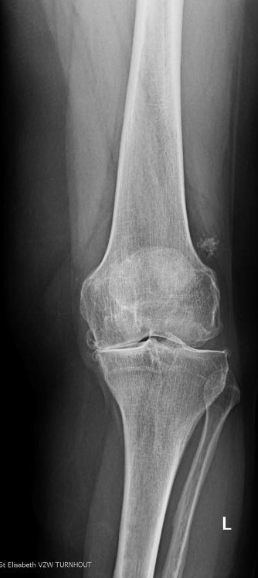

Deze ingreep kan gebeuren bij patiënten waarbij de slijtage (artrose) beperkt is tot één compartiment van de knie. Dikwijls zien wij deze kraakbeenschade ontstaan na een vroeger uitgevoerde meniscusoperatie of bij uitgesproken asafwijkingen van het onderste lidmaat. Het doel van een osteotomie (kanteloperatie) is de druk op de pijnlijke kant van de knie (meestal het binnenste/mediale compartiment) te verminderen. Door de as van het onderbeen (tibia) te wijzigen, verschuift de kracht naar de niet-pijnlijke kant van de knie waar het kraakbeen nog intact is. Hiervoor wordt de knie in een lichte X-stand (valgus) of O-stand (varus) geplaatst. Door deze ingreep kan de evolutie naar verdere slijtage afgeremd of zelfs volledig gestopt worden. Indien de knie toch verder zou evolueren naar een totale artrose en het plaatsen van een totale knieprothese nodig wordt, hebben we deze prothese kunnen uitstellen zonder het resultaat ervan te compromitteren.

Een radiografie waar de heup, de knie en de enkel op één opname te zien is (full leg) is noodzakelijk. Per casus kan beslist worden tot het nemen van een MRI en zelfs het uitvoeren van een kijkoperatie (artroscopie). De bedoeling is met volledige zekerheid de status van het gezonde kraakbeen te beoordelen.